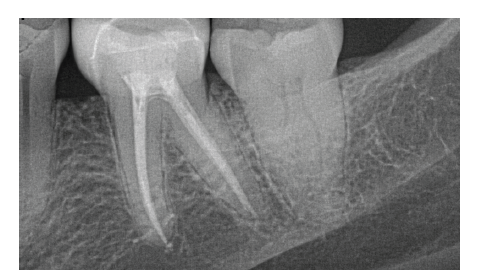

Presentation of the clinical case of deep distal caries with symptoms of acute pulpitis on tooth 46 in an 80-year-old patient:

Presentation of the clinical case of deep distal caries with symptoms of acute pulpitis on tooth 46 in an 80-year-old patient…